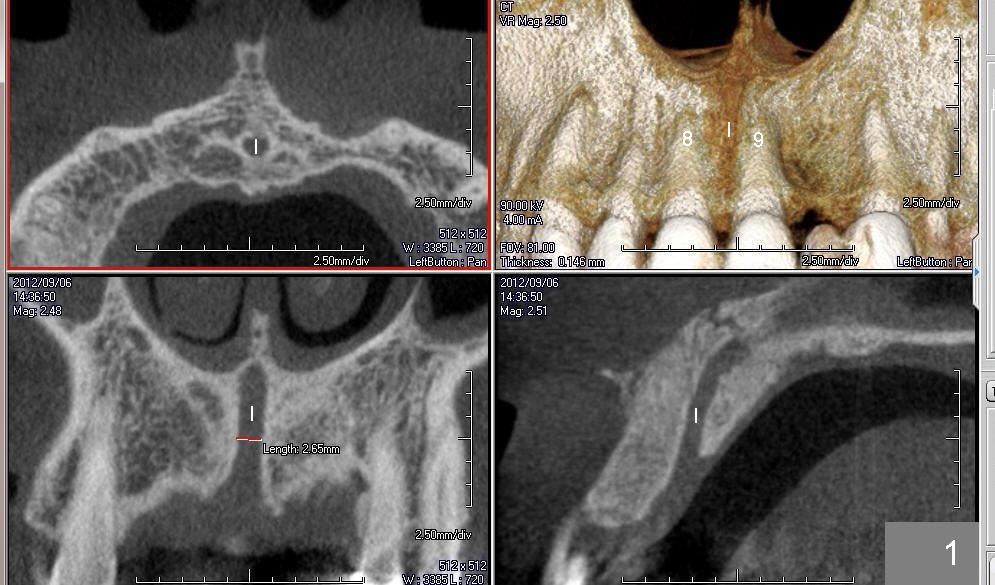

CT研究表明当切牙管小时(图一:I(Incisive Canal),二毫米左右),它比较对称,位于中切牙牙根之间(8,9)。当它大时(五六毫米),它可能对称(图二)或者不对称(图三,四),接近一个(图三,四)或者两个(图二)牙根,造成植牙困难。